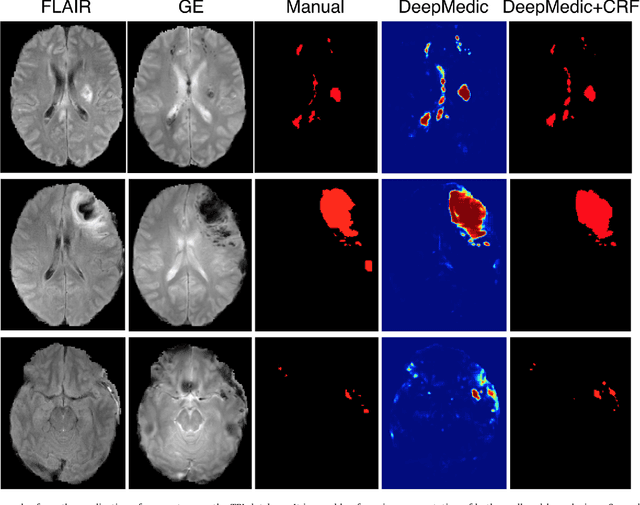

Abstract:We propose a dual pathway, 11-layers deep, three-dimensional Convolutional Neural Network for the challenging task of brain lesion segmentation. The devised architecture is the result of an in-depth analysis of the limitations of current networks proposed for similar applications. To overcome the computational burden of processing 3D medical scans, we have devised an efficient and effective dense training scheme which joins the processing of adjacent image patches into one pass through the network while automatically adapting to the inherent class imbalance present in the data. Further, we analyze the development of deeper, thus more discriminative 3D CNNs. In order to incorporate both local and larger contextual information, we employ a dual pathway architecture that processes the input images at multiple scales simultaneously. For post-processing of the network's soft segmentation, we use a 3D fully connected Conditional Random Field which effectively removes false positives. Our pipeline is extensively evaluated on three challenging tasks of lesion segmentation in multi-channel MRI patient data with traumatic brain injuries, brain tumors, and ischemic stroke. We improve on the state-of-the-art for all three applications, with top ranking performance on the public benchmarks BRATS 2015 and ISLES 2015. Our method is computationally efficient, which allows its adoption in a variety of research and clinical settings. The source code of our implementation is made publicly available.